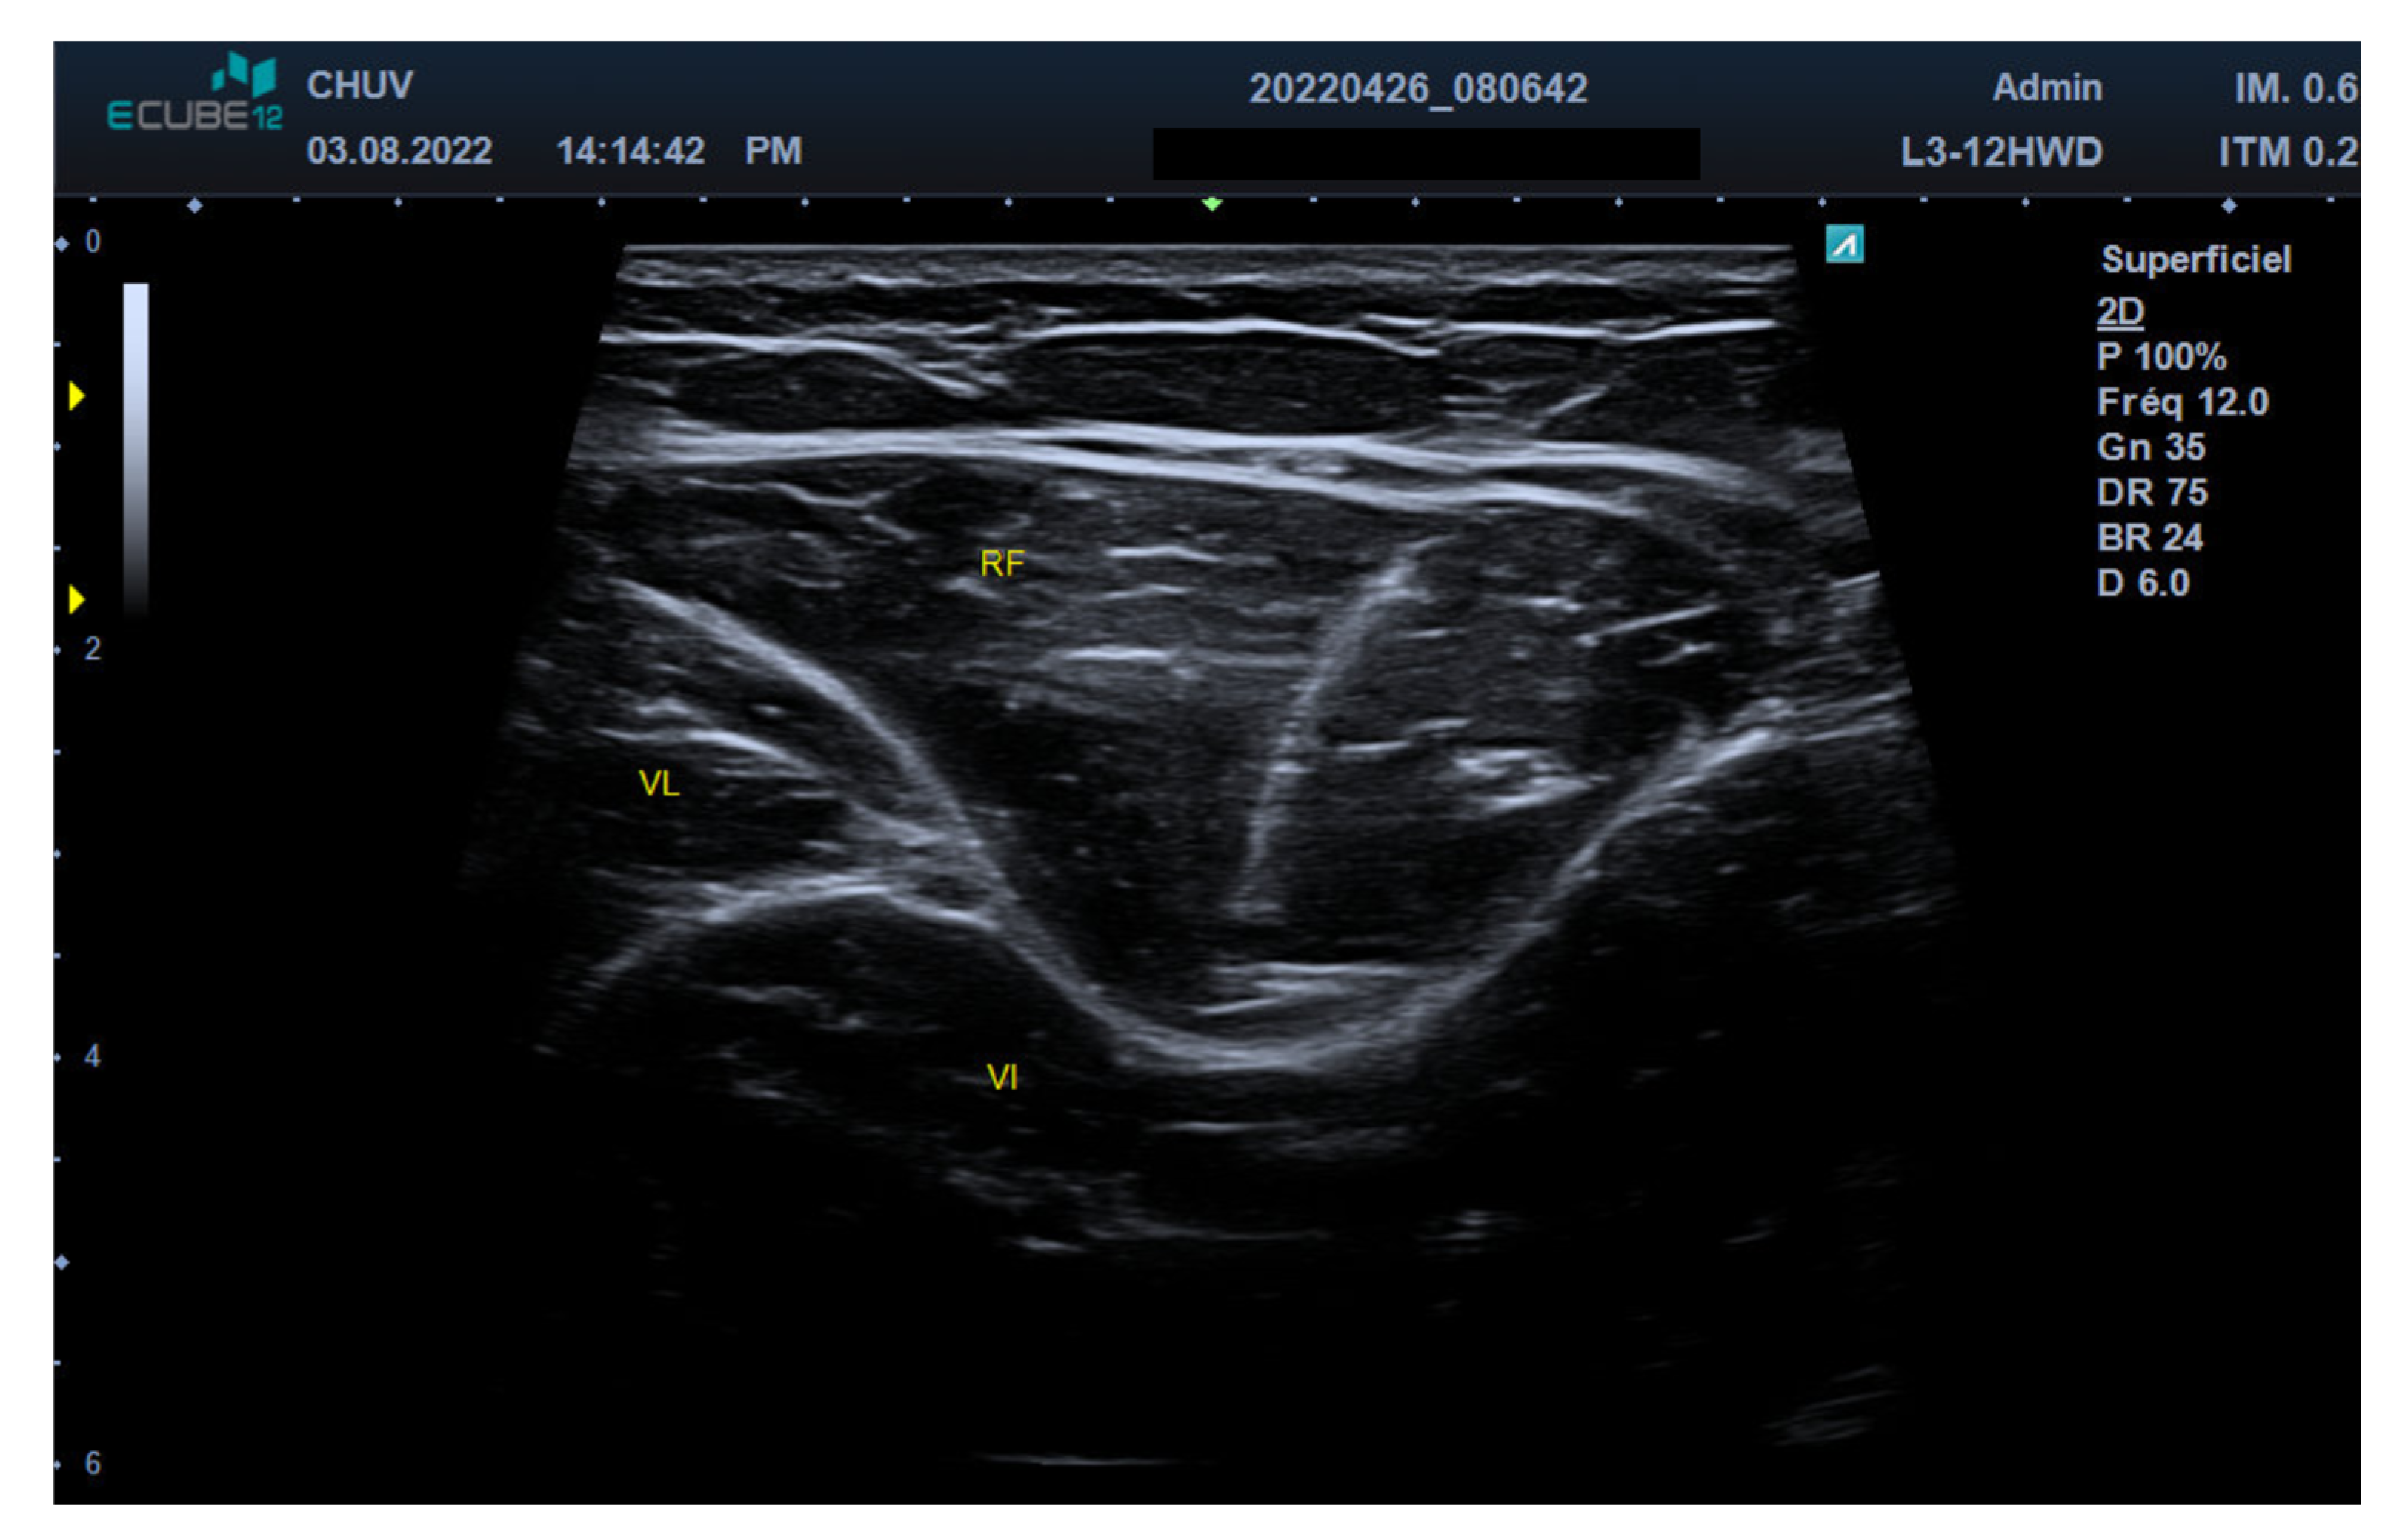

2.2. Ultrasound Technique and Anatomical Identification

2.3. Motor Nerve Branch Identification